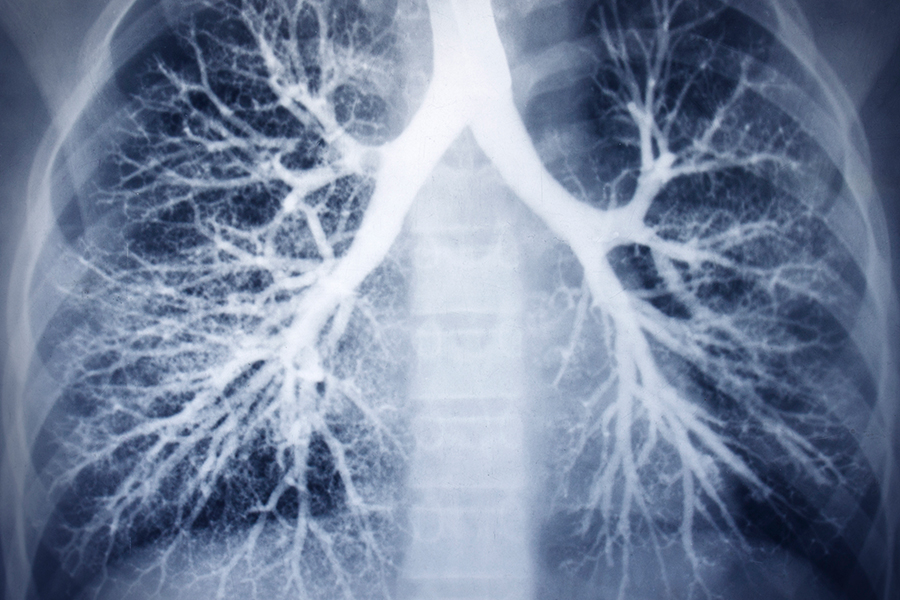

Бронхоэктатическая болезнь – патология бронхов врожденного или приобретенного характера, в процессе развития которой органы дыхания поражает гнойное воспаление с одновременной деформацией бронхиальной стенки. Свое название патология получила от медицинского термина «бронхоэктазы», что означает расширение внутреннего пространства бронхов под влиянием воспалительного процесса или вследствие врожденной аномалии.

• Рентгенограмма легких. На снимке больного заметны деформация контура бронхов, ячеистая структура тканей, уменьшение объема пораженной части бронха.